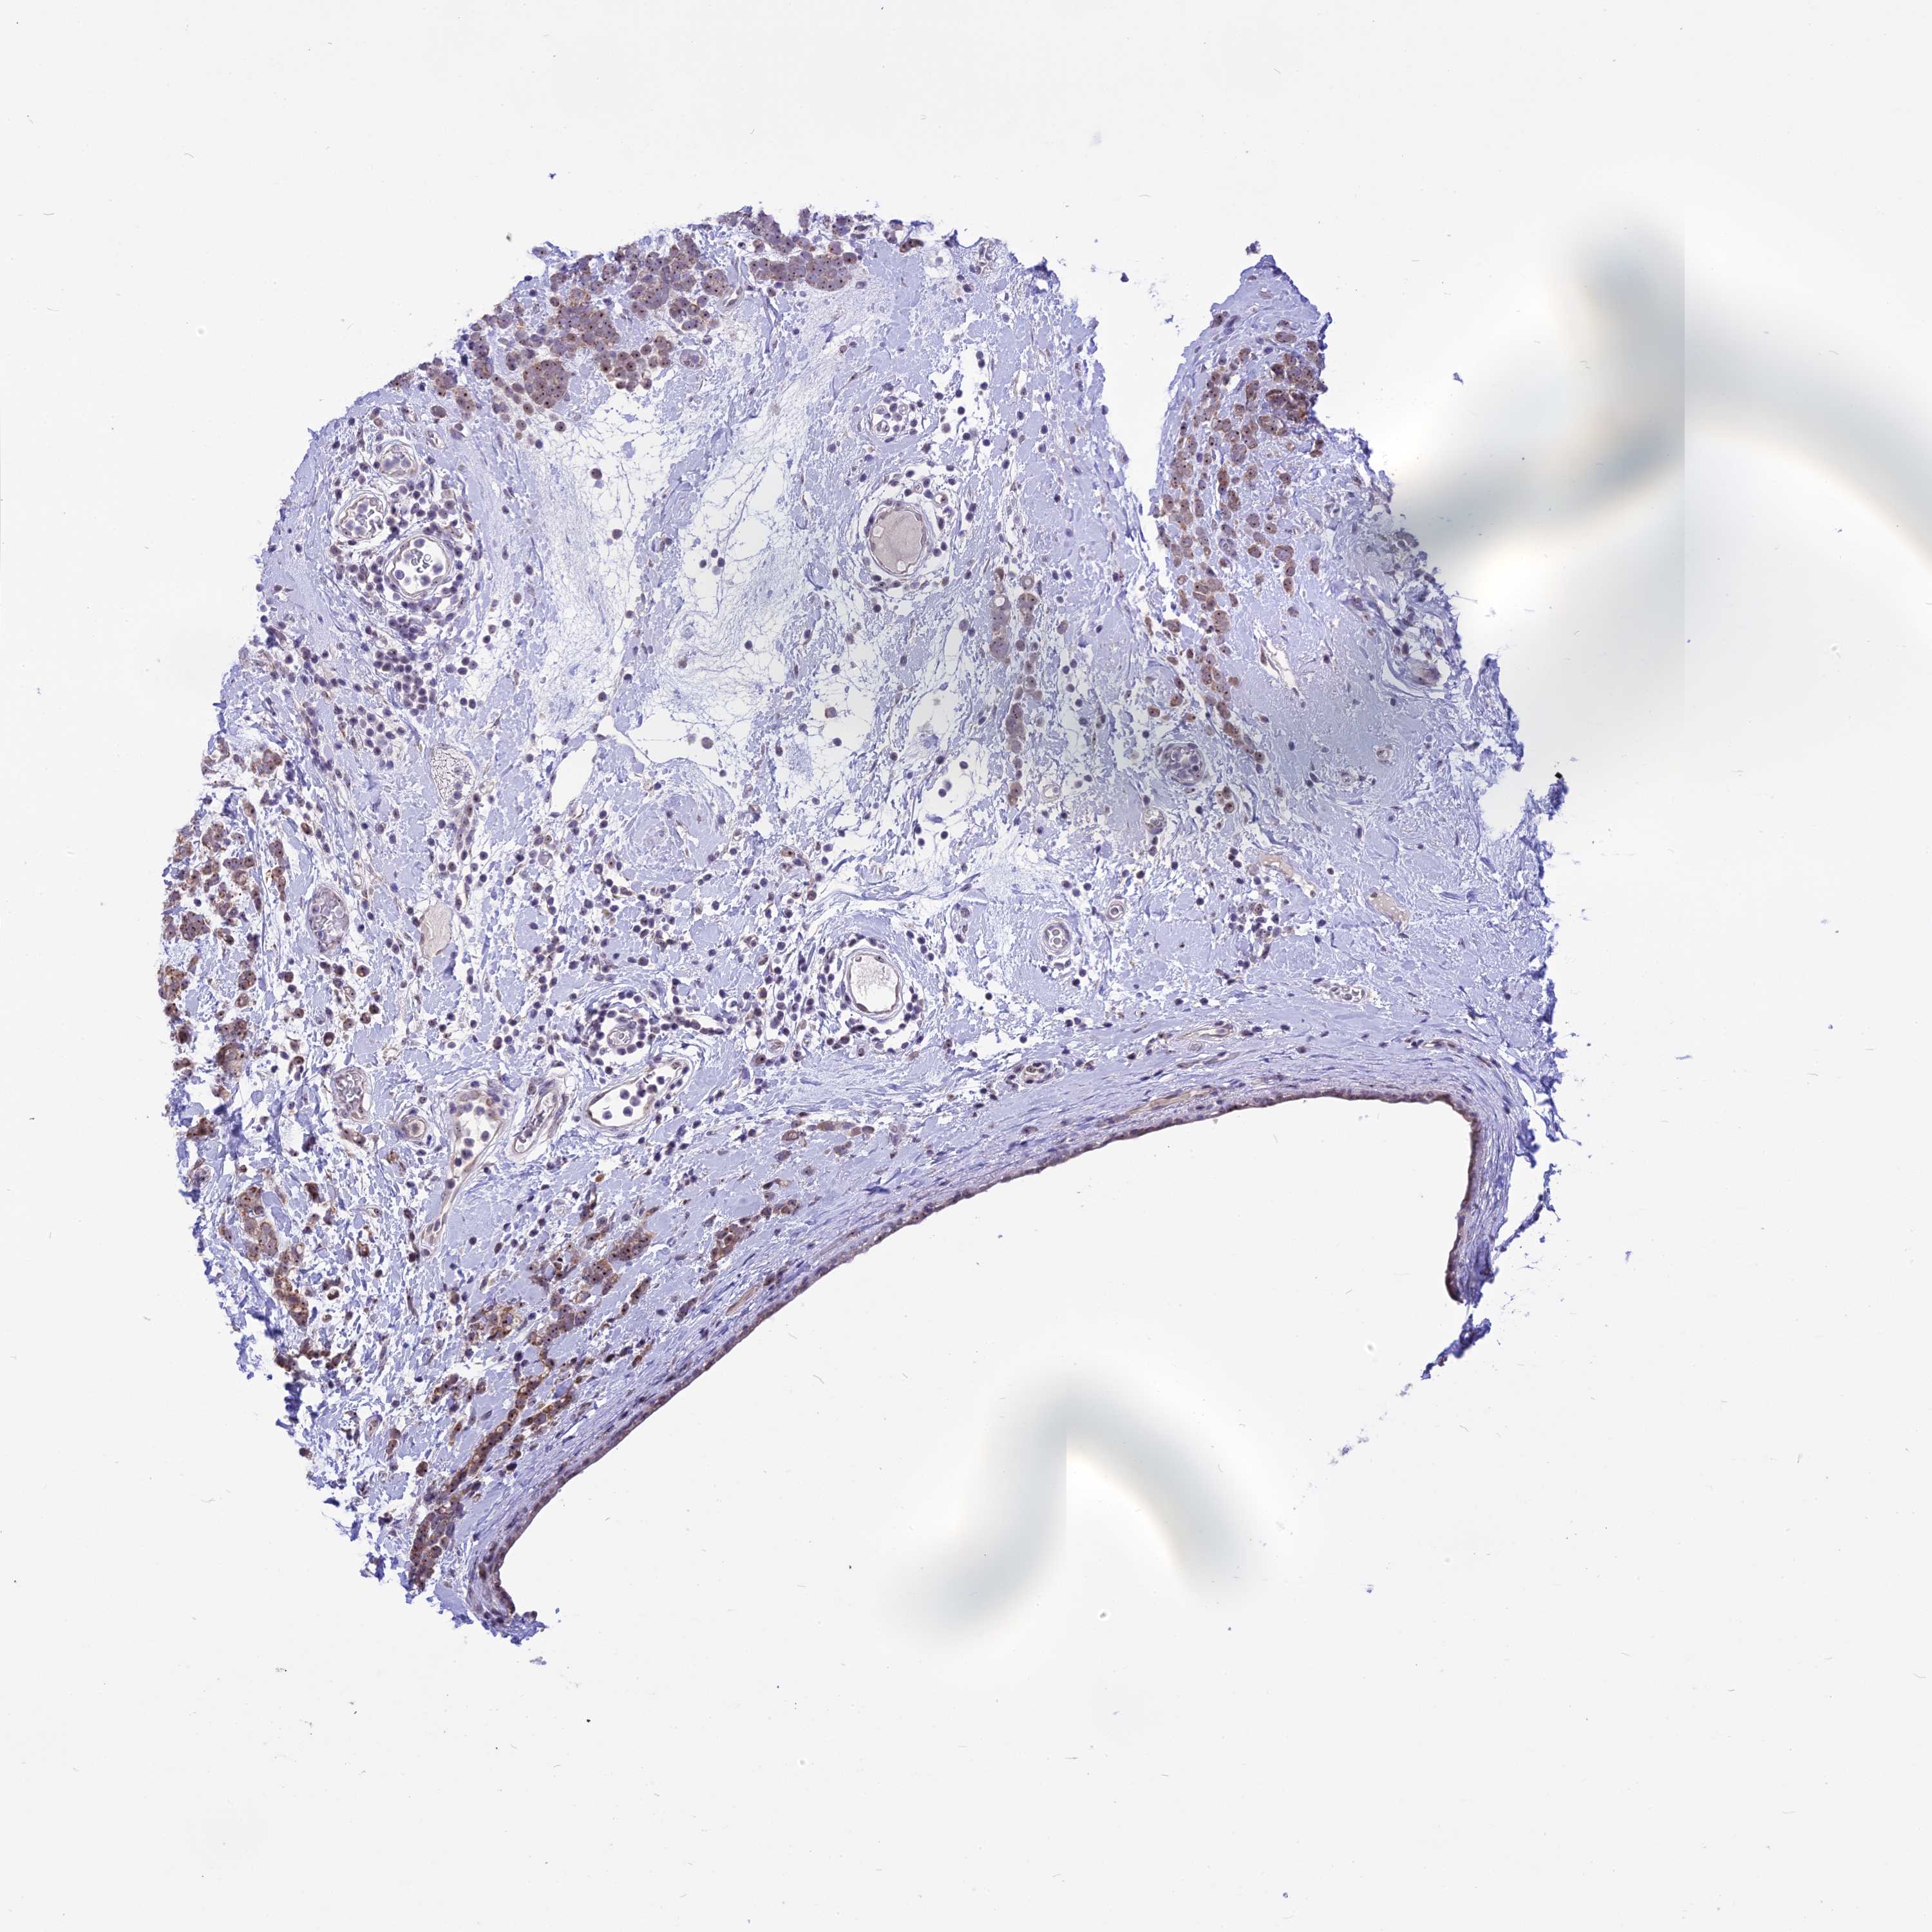

CANCER BREAST CANCER Show tissue menu

BRCA TCGA BRCA VALIDATION PROTEIN EXPRESSION

Breast cancer

Human cancer